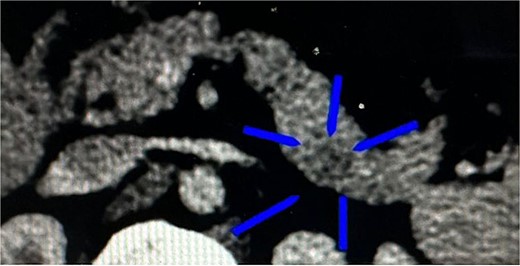

A 23-year-old woman with a history of subclinical hypothyroidism treated with levothyroxine presented with episodes of paresthesia in the lower extremities and nocturnal sweating related to hypoglycemic episodes. Subsequently, she was hospitalized for disorientation, tonic–clonic seizures, and hypoglycemia levels as low as 17 mg/dL. The study protocol was initiated with an abdominopelvic computed tomography (CT) scan with contrast, revealing an ill-defined ovoid structure of 26 mm at the tip of the pancreatic tail with an average value of 65 Hounsfield units (HU; 89 HU in the rest of the parenchyma) and dimensions of 17 mm × 15 mm × 9 mm (Fig. 1). Laboratory analysis revealed the following: 214 ng/dL of insulin-like growth factor type I (IGF-1), 55.40 mIU/L of insulin, 10.1 ng/mL of C-peptide, and >1000 IU/ml of anti-peroxidase antibodies. Endogenous hyperinsulinism secondary to an insulinoma was diagnosed, making the patient a candidate for minimally invasive surgical resolution.

CT of the transverse plane of the pancreas revealed an ill-defined ovoid structure at the pancreatic tail tip.